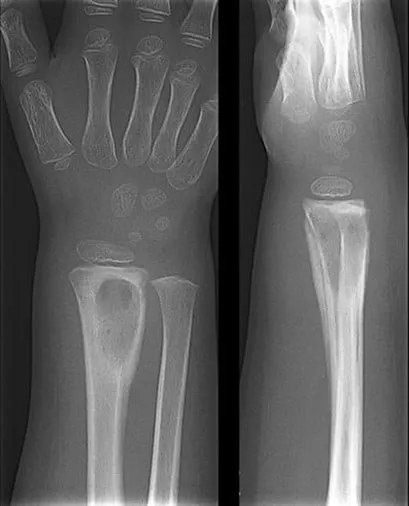

- Imaging: X-ray findings (periosteal reaction, lytic lesions) appear late (after 10-14 days). MRI is the investigation of choice for early diagnosis.

- X-ray: May be normal for 7-10 days. Late signs: lytic lesions, periosteal reaction.